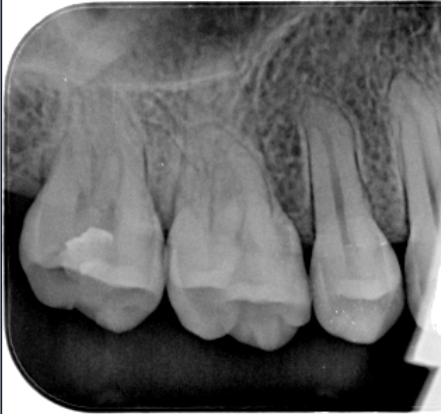

牙医-马小寒【实操病例】

右上6号牙位的近中,可见隐约龋坏

◆去腐完成之后

在以树脂充填为前提的案例中,无需过度制作颌面的鸠尾固位型,橡皮障下隔湿,是临床粘结操作技术成功的重要保障。酸蚀剂在使用的时候,需要尽量避免对邻牙的伤害